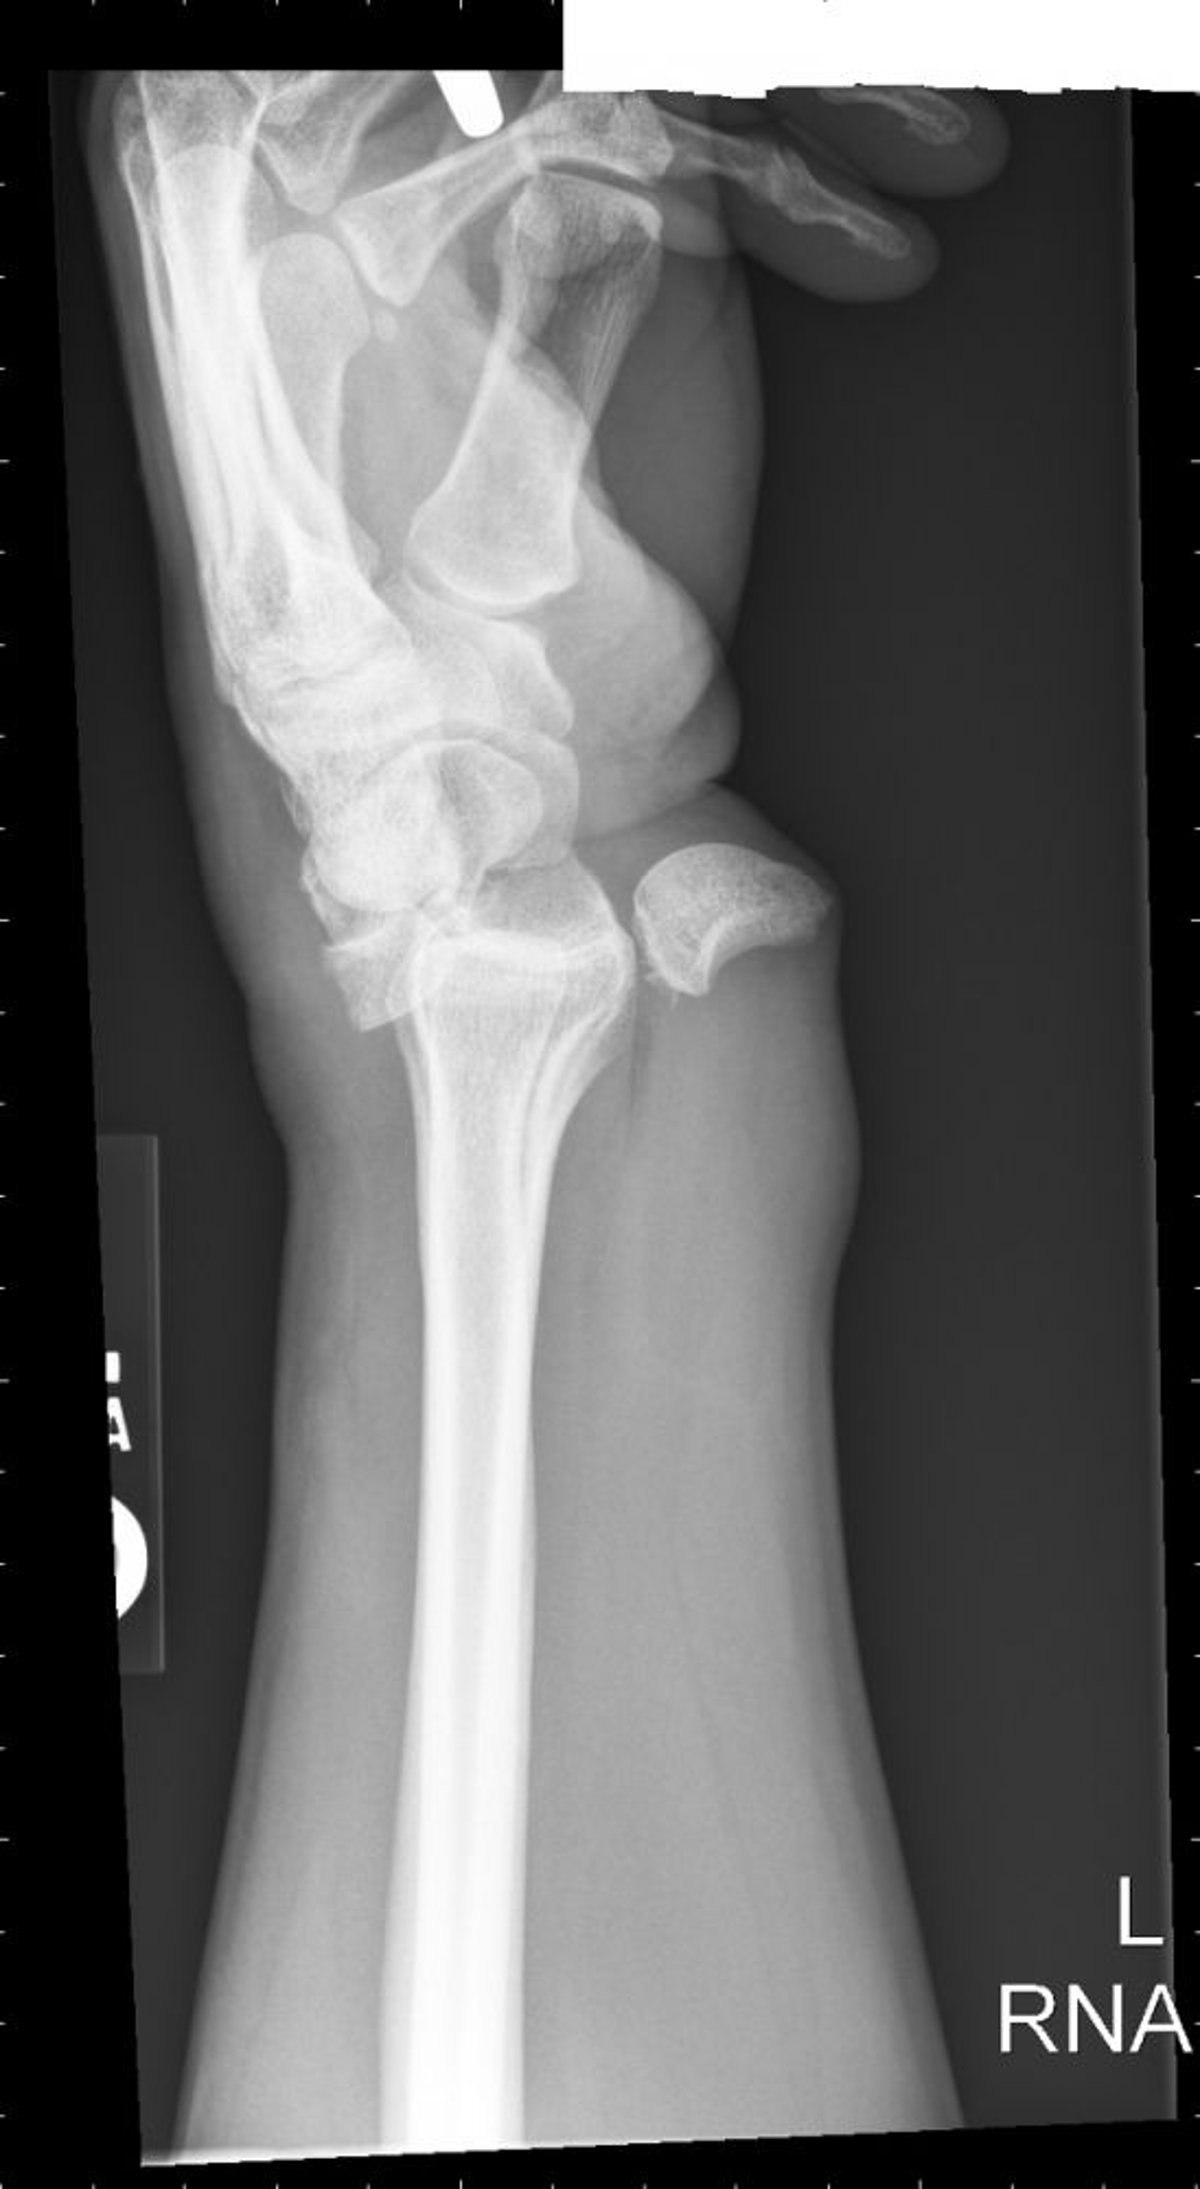

Luxación del semilunar

La luxación del semilunar se traduce en una configuración de taza de té derramado.

Image courtesy of Danielle Campagne, MD.